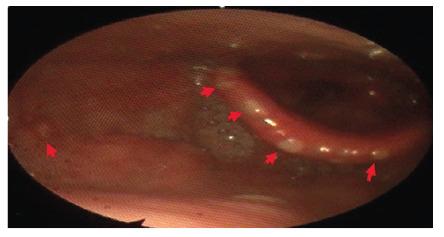

强力霉素致食管炎合并口腔溃疡及喉炎1例。

A Case of Doxycycline-Induced Esophagitis Accompanied by Oral Aphthous Ulcers and Laryngitis.